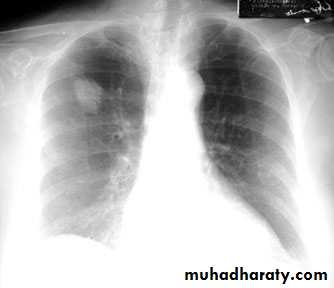

Bronchopneumonia